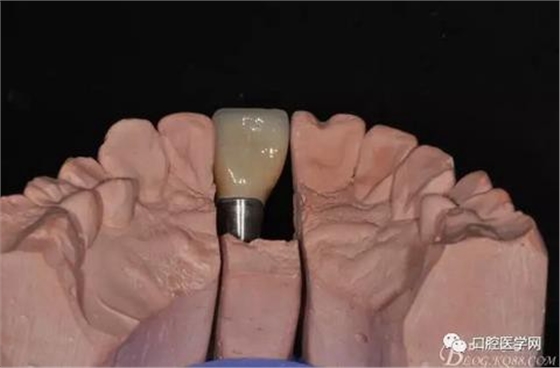

圖16 修復(fù)基臺(tái)模型頜面照

圖17 烤瓷冠唇側(cè)照

圖18 烤瓷冠舌側(cè)照